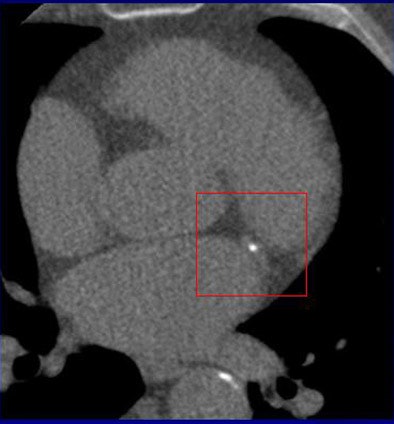

![]() |

| Motion artifacts were graded subjectively on a scale of 1-3, and the extent of motion artifacts was found to have a significant effect on calcium scores. The average absolute deviation from the reference score increased with increasing motion scores, from 13% to 46% for the Agatston score, and from 7% to 37% for the mass score. |